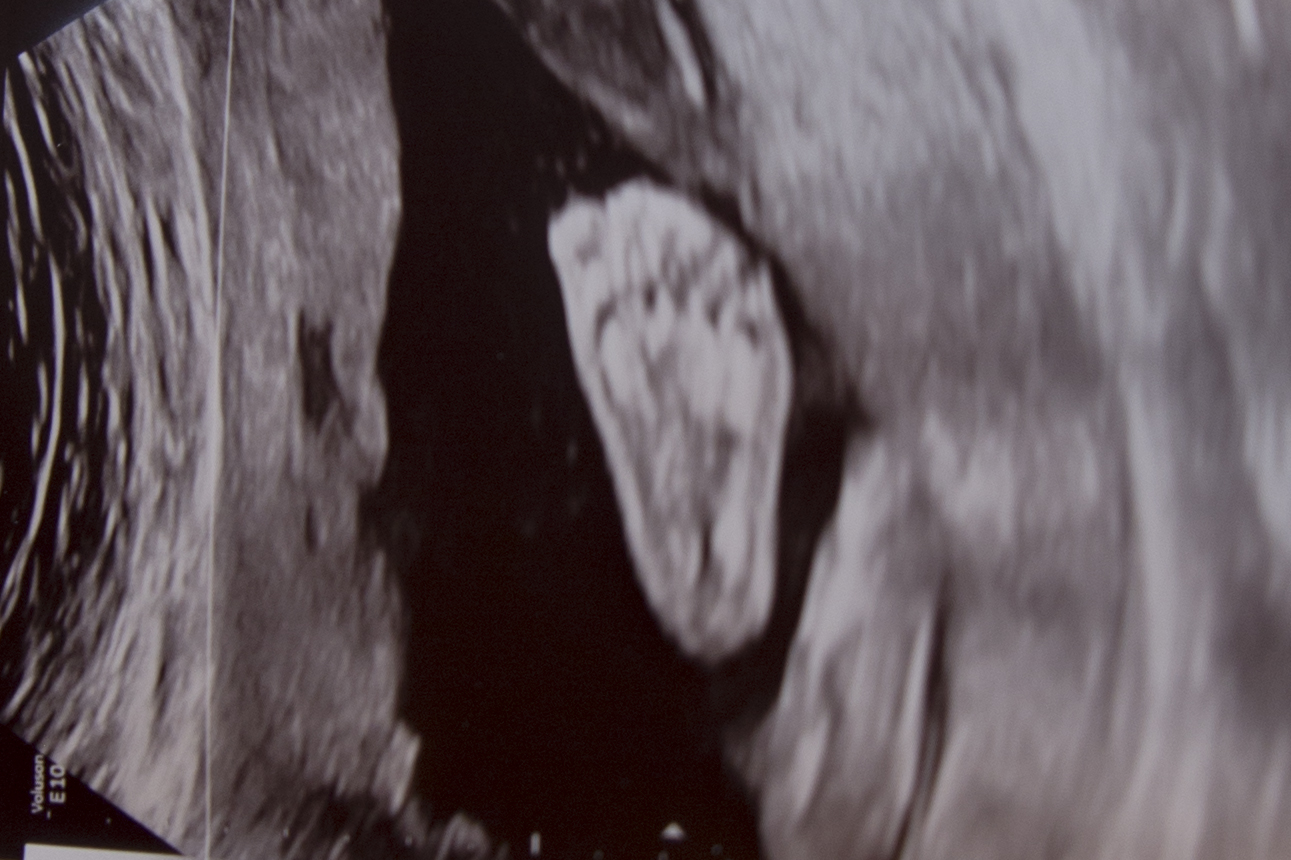

And the doctor caught a scary picture of him yawning